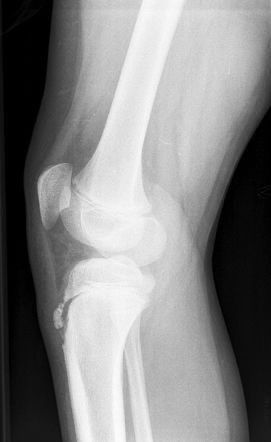

Fracturas

Ocurren por caídas o accidentes y requieren diagnóstico inmediato mediante radiografías o tomografías. El Dr. Sjöstrand realiza inmovilización con férulas o yesos, y si es necesario, procedimientos quirúrgicos para asegurar la correcta consolidación ósea.

Artrosis

Es una enfermedad degenerativa del cartílago que provoca dolor, rigidez y limitación de movimiento. El Dr. Sjöstrand realiza evaluaciones completas para determinar el grado de desgaste articular y recomienda tratamientos que van desde fisioterapia, medicamentos y cambios de hábitos, hasta cirugías de reemplazo articular si es necesario.